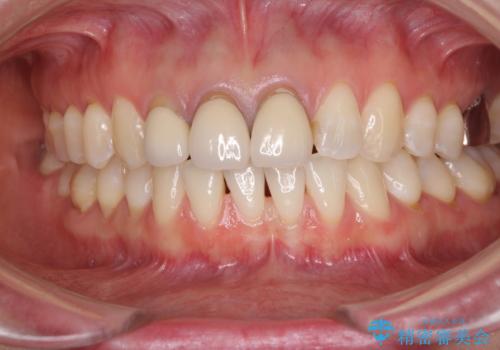

前歯の審美歯科治療 オールセラミッククラウンと部分矯正

- 上の前歯のセラミッククラウンが古くなったことと、下の前歯のデコボコを気にして来院された患者様です。

補綴治療に先立ち、下顎前歯の部分矯正を行い、前歯の咬み合わせの安定性向上を図りました。

当初は上顎の補綴治療のみを希望されていましたが、仮歯装着期間に上下の前歯の接触が気になったため、部分矯正を行うこととしました。

審美面と合わせて機能面も改善され、患者様には大変満足していただきました。